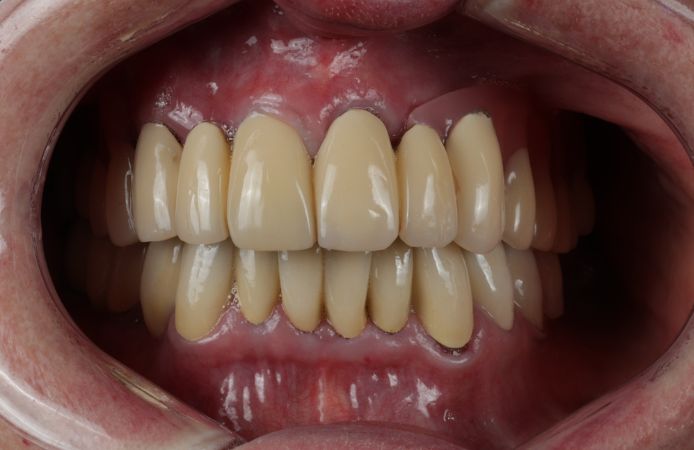

Figure 2.

Initial clinical situation after removal of failing telescopic bridge.